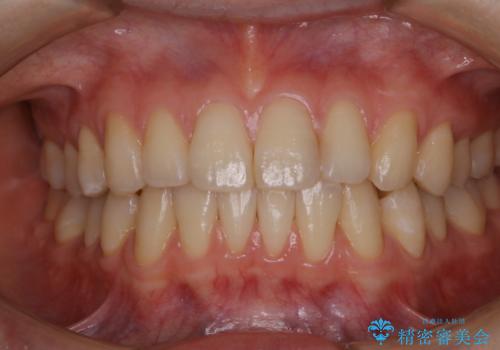

マウスピース矯正終了後にPMTCでよりきれいな歯に

- インビザラインでのマウスピース矯正が終了したため、きれいにクリーニングして口元を明るい印象にしたいとのことでした。PMTC60分コースを行いました。

矯正治療やセラミックなどによる被せ物の治療終了のタイミングではクリーニングを行い、汚れや着色の除去、歯と歯の間・歯と歯肉との境目などのケアをしっかりすることをおすすめしています。

ご自身での歯ブラシ・セルフケアを行うと同時に、定期的なクリーニング(PMTC)を行うことで、いつまでも健康な歯を保つことができます。